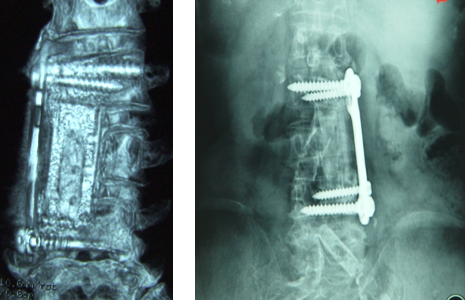

注册证名称:医用纳米羟基磷灰石/聚酰胺66复合骨充填材料

1.优异的生物相容性和生物活性

3.弹性模量更接近自体骨,有效减少应力遮挡

4.有效降低沉降率、塌陷率

● 椎体间融合及椎体切除后缺损的修复